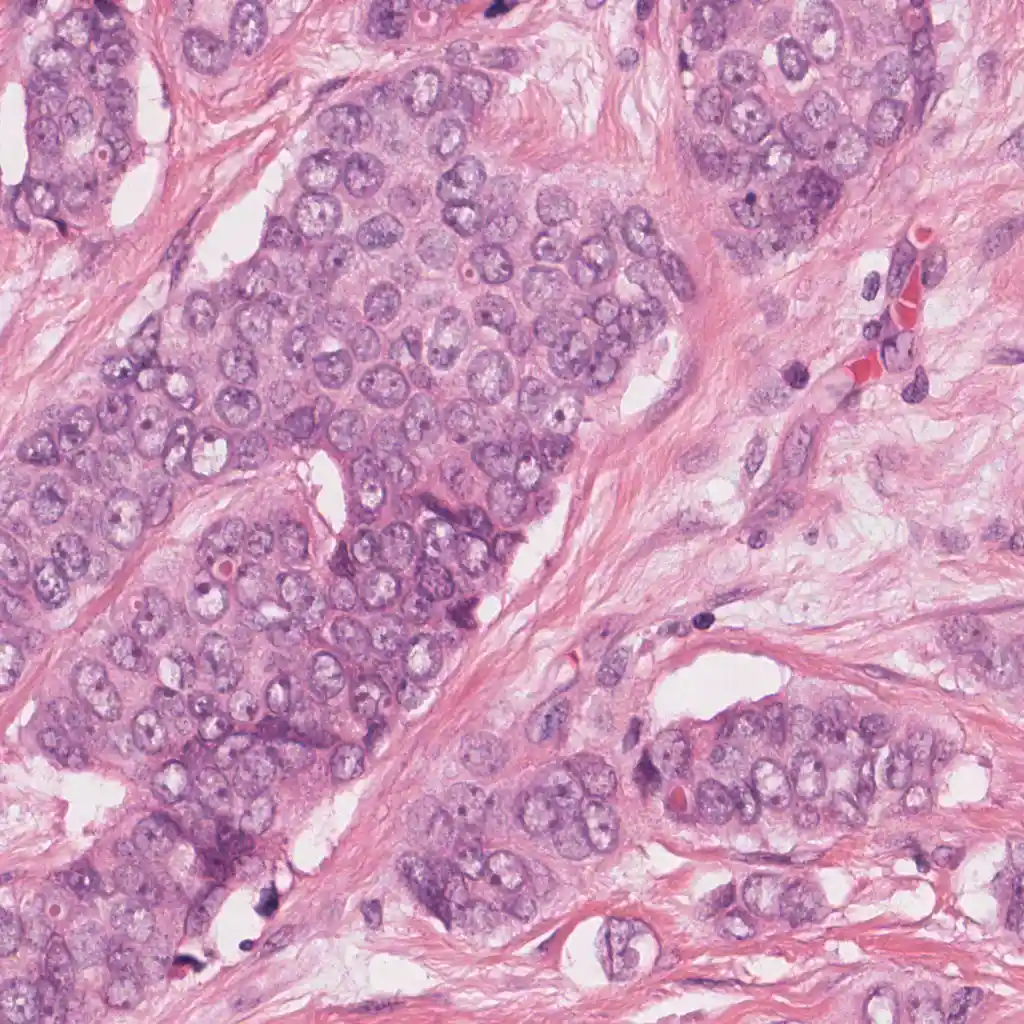

One of the major difficulties in histopathology image analysis is apperance variability. For example, when performing mitosis detection, many false positives can arise when the histopathology slide is overstained. This Python code, adapted from the original MATLAB implementation, performs staining unmixing (separation of the hematoxylin and eosing stains) and apperance normalization. It is based on the method described in [1]. Some examples of staining normalization can be seen in the figure below.